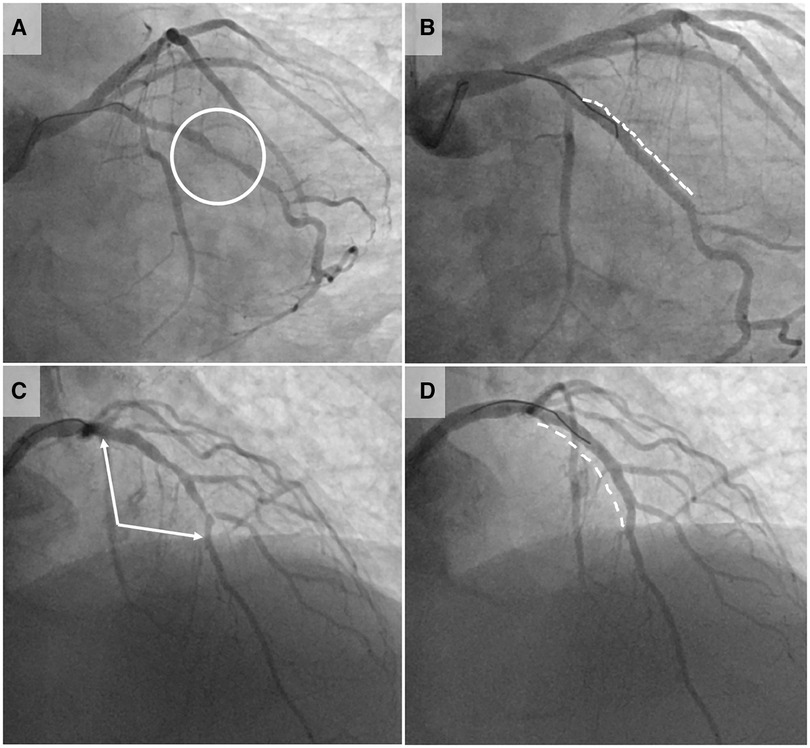

All procedures were done by a single operator (JH), assisted by four dedicated Catheterization Laboratory technician (range between 2 and 9 procedures per assistant). In 4 patients, two lesions were treated robotically during the same procedure, and one other patient underwent manual treatment of an additional lesion (not planned to be treated robotically). The majority of robotically treated lesions (72%) were type B2 or C, with 24% bifurcation lesions requiring side branch intervention. Figure 2 shows an example of two lesions undergoing robotic PCI. Median procedure time was 47 min [interquartile range: 29 min], robotic time 37 [34] min, and fluoroscopy time 11.5 [10.5] min. Median dose-area-product was 5,118 cGy*cm2 [3,768] and mean contrast volume used was 194 ± 64 ml.

Figure 2. Case illustrations of robotic-assisted PCI. Pre- and post-interventional coronary angiography images of two exemplary lesions treated by robotic-assisted percutaneous coronary intervention (RA-PCI). Panels (A) (pre-interventional) and (B) (post-interventional result) illustrate the first case conducted robotically at our institution: a focal lesion of the first marginal branch (circle in panel A). After manual intubation of the left main with a guiding catheter, the robotic system was connected. The procedure was thereafter conducted robotically by the operator in the cockpit, whereas coronary device exchanges were done by the Catheterization Laboratory technician. The lesion was treated with predilation, implantation of one stent (dashed line in panel B) and postdilation. This simple first case pointed to one challenge faced by the Catheterization Laboratory technicians. The coronary devices need to be exchanged manually after opening the single-use cassette. The implemented fixation gadget on the cassette does not provide sufficient guidewire fixation to guarantee wire immobilization during device exchange process, allowing the wire to be pulled or pushed during manipulation. Besides extensive training of the Catheterization Laboratory technicians, the selection of straightforward lesions with low risk for predilation-related dissections is important during the implementation phase of RA-PCI. Panel (C) (pre-interventional) and (D) (post-interventional result) show one of the latest cases (74 year-old patient) conducted completely robotically. The lesion involved the proximal and mid left anterior descending artery (LAD) including the bifurcation of the second diagonal branch (between arrows in panel C). This bifurcation lesion required the use of two coronary guidewires, which necessitated the technician to switch the wires between drive lane and “parking” position several times. Two stents were implanted in the LAD (dashed line in panel D) and the diagonal branch was re-wired and fenestrated all robotically.

RA-PCI has a major impact on the workflow of Catheterization Laboratory technicians as they need to get adapted to load the robotic system with guidewires and to exchange coronary device-catheters. Although the robotic cassette features a fixation system for the guidewire, the first case (Figure 2) illustrates that guidewire movement during device exchange represents a limitation. Aside from specific training of Catheterization Laboratory technicians in terms of wire handling during device exchange, it is advisable to initiate a RA-PCI program focusing on the intervention of simple lesions. Furthermore, device exchange times are longer than during manual PCI due to additional steps needed (opening of the cassette, removal of the guidewire and the used device from their respective drive lanes and replacing the guidewire and the new device in their lanes followed by closure of the cassette), and the unusually high level of manipulation of the guidewires and devices due to the fix position of the robotic arm. We were unable to observe the expected reduction in manpower needed for RA-PCI. Although the primary operator mainly acts from the cockpit, a tableside assistant familiar with the robotic system is needed. Moreover, an additional cathlab nurse is needed to supply the tableside assistant with PCI material, to administer medication to the patient and to document the peri-procedural course.